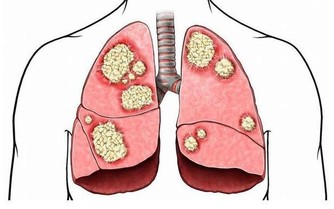

1、憂鬱症 患憂鬱症的人,在吃過香蕉後,感覺好很多。因為香蕉含胺基酸,會轉化成血清促進素,令人放鬆心情、提升情緒。 2、貧血 香蕉鐵質含量高,能刺激血液內的血紅素。 3、高血壓 香蕉含極高量的鉀,但鹽分低,最理想的降血壓食物。最近,美國食品及藥物管理局宣布,允許香蕉業宣傳「香蕉能降低高血壓和中風機率」。 4、腦力 在英國Twickenha就有200名學生,為了要提升腦力,幫助考試,在學期開始,於早餐、午餐和午休時,都吃適量香蕉。研究顯示,含豐富鉀質的香蕉,能提高學生的專注力,對他們讀書有所幫助。 5、便秘 香蕉的纖維質很高,可幫助恢復腸胃正常活動,消除便秘,無需服用清瀉劑。 6、宿醉 香蕉牛奶加蜜糖可以幫助解酒。香蕉放鬆胃部,蜜糖提升血糖平穩,抒緩精神和製造碳水化合物。 7、心絞痛 香蕉對身體有一種天然的制酸性,有鎮痛作用。 8、早上無精打彩 早餐後午飯前,吃少量香蕉可保持血糖平穩。 9、蚊叮蟲咬 用香蕉皮內部輕擦患處,可消腫消炎。 10、緊張 香蕉的維生素B含量高,可幫助抒緩神經系統。 11、體重超重 奧地利心理學學校研究發現,工作壓力大,使員工會不斷進食甜食和零食去抒緩情緒。研究員對5000名醫院的病人做研究,肥胖症狀者,通常都是工作壓力非常大的工作。 研究總結認為,要避免引起對抒緩情緒食物的慾念,就應該約每兩小時吃一點高碳水化合物的食物,以防止身體內的血糖升高。 12、胃潰瘍 香蕉是調理腸胃失調的食方,因為香蕉有著柔軟的纖維而且柔滑。對於長期患者來說,香蕉是唯一可以進食的未煮熟食物,而不會有不良反應。香蕉還可以中和胃酸和減少疼痛。 13、體溫控制 在不同國家、地區和文化中,都有把香蕉作為一種「降溫」的水果,可以用作降低身、心的熱度。在泰國,孕婦為了使嬰兒出生時有較為涼快的環境,臨盆時就會吃香蕉。 14、戒煙 香蕉可以幫助戒煙。香蕉含維生素B6和B12,也含鉀和鎂,可以復元戒煙者,因為沒有了尼古丁刺激的影響。 15、壓力 香蕉所含的鉀,可以調節心跳使之正常化,從而將氧氣順利送到大腦,以及調節身體的水分。當受到壓力緊張時,我們的新陳代謝就會加快,因而使鉀的含量下降。鉀含量高的香蕉,正好作補充。 16、中風 據著名醫學雜誌「The New England Journal of Medicine」的研究指出,長期吃香蕉,中風死亡的機會率大大降低40%。